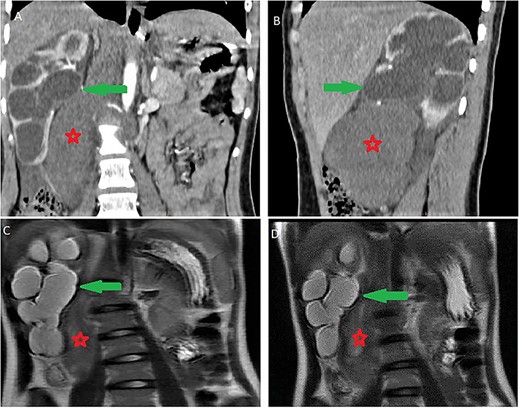

On magnetic resonance imaging (MRI), tumor signal was heterogeneously high in T2-weighted images, while iso to low in T1-weighted images delayed heterogeneous enhancement with some septa and areas of necrosis (Fig. 2).

Abdominal MRI showing a retroperitoneal mass; (A and B) axial T2-weighted images show heterogeneous high signal in the lesion; (C and D) axial T1-weighted image, before (C) and after (D) dynamic sequences with contrast showing a delayed heterogeneous enhancement with some septa and areas of necrosis within the mass.